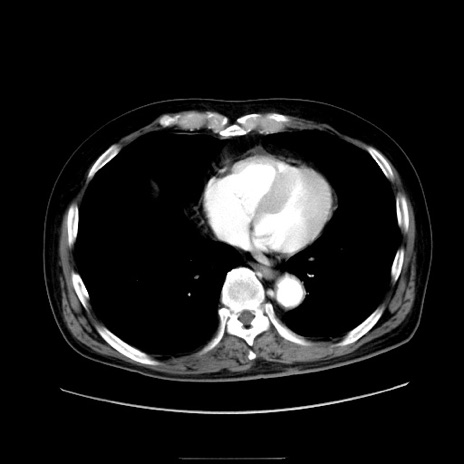

症例30(横断像)

【症例】80歳代男性

【主訴】臍周囲痛

【現病歴】約6時間前から臍下部痛が出現。次第に腹部膨隆・背部痛も生じてきたため来院。背部痛の場所は変化しない。

【身体所見】意識清明、BT 36.3℃、BP  131/87mmHg、P 87bpm、SpO2 100%(RA)、臍周囲自発痛・圧痛あり、反跳痛なし、自発痛部位に一致して板状硬あり、腹部膨隆、腸雑音減弱、CVA tenderness両側陰性。

【データ】WBC 19600、CRP 0.33